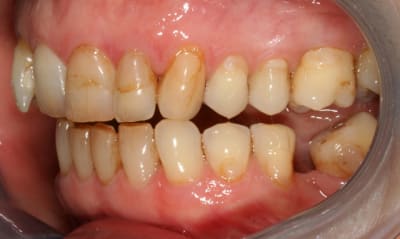

pour l'occlusion, voilà les photos, il y a effectivement une classe II, plus marquée à droite qu'à gauche

il y a l'absence de la 36 depuis quasiment l'enfance, l'occlusion est calée comme ça depuis plus de 30 ans et ça ne bouge pas

il n'y a pas (ou peu) de supraclusion (overbite je crois que c'est ça)

il n'y a aucun problème musculaire ou articulaire

Ortho (sans chirurgie) l'axe des dents est hyper moche pour l'occlusion

Tu auras une meilleure harmonie occlusale, et les secteurs post inférieurs seront en équilibre.